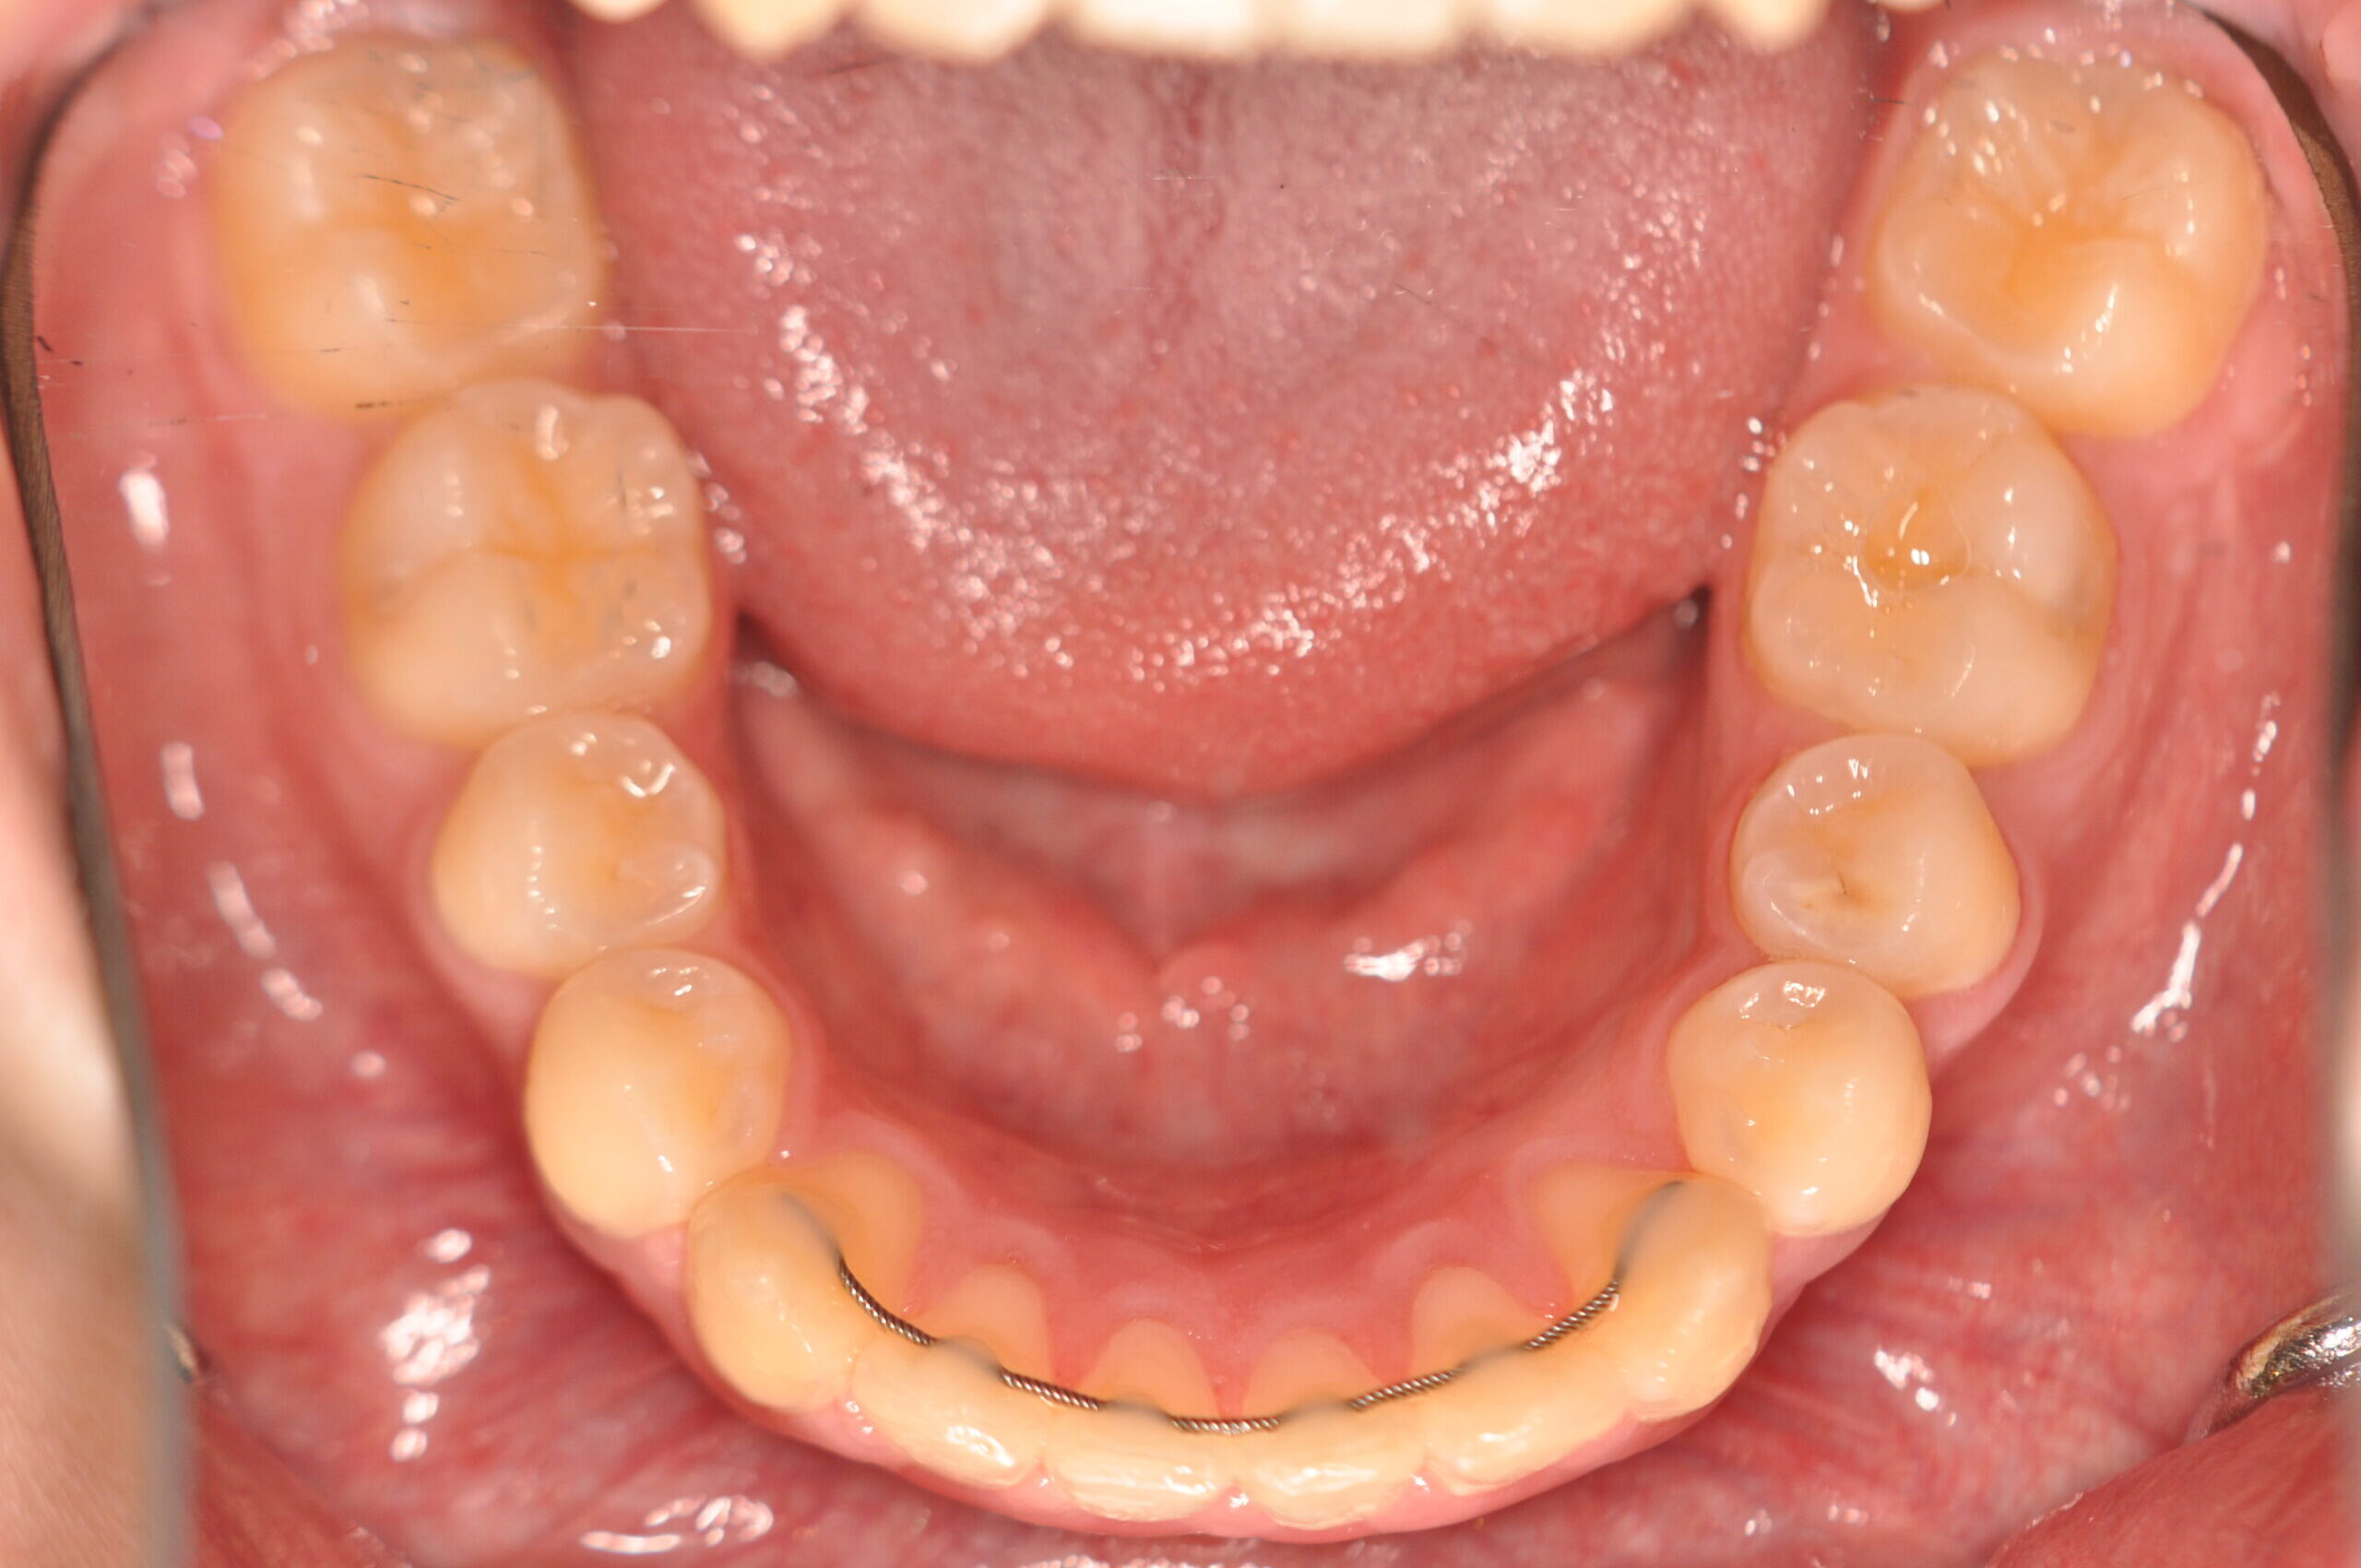

| 治療内容の詳細 | 初診時16歳の男性で、歯のがたつき、かみ合わせを気にされ来院しました。 検査の結果、アングルⅡ級2類不正咬合と診断しました。 治療としては、非抜歯の上、セルフライゲーションブラケット装置(デーモンシステム)で配列を行いました。 同時に顎間ゴムにて咬合関係の改善を行いました。 治療期間は、1年6ヶ月でした。 |